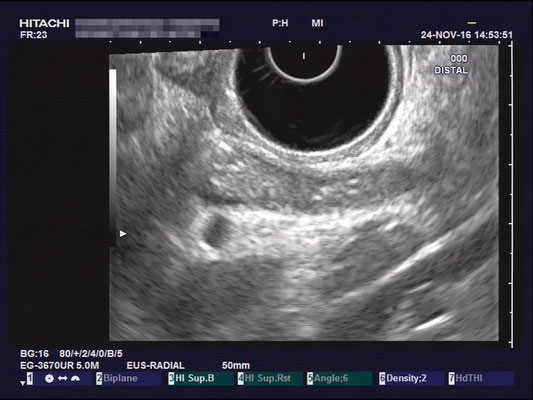

Common bile duct (CBD)

For a full examination of the common bile duct (CBD), we want have a great view of the most distal part, at the duodenal papilla. Optimally we can identify the double duct sign (or as I like to call it the "money shot") and work our way towards the liver. The CBD is joined by the hepatic artery and Portal vein, making up the Glisson's Triad. Using the doppler signal will help differentiate the vessels.

The most observant viewers will have noticed that not all images above depict normal findings but some abnormalities. (my bad ;)